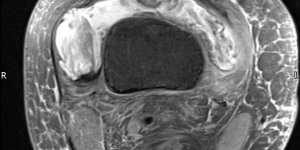

Lipoma Arborescens | Cases

Published on Dec 17, 2020

(2016) Patient (male) aged 44 attends physical therapy department with right knee pain. He gives a 5 year history of knee pain. He has noticed on and off swelling in the right knee. The clinician notices high BMI. On knee exam, there is slight swelling noticed on the knee. ROM is full with slight tightness at end range flexion and extension. [...] Read more